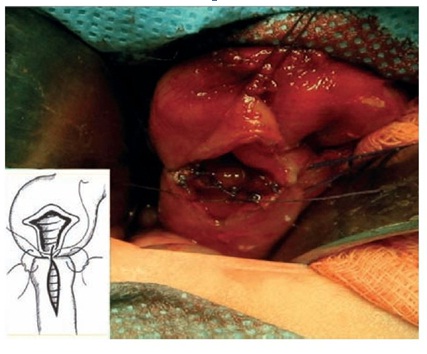

En la exploración se evidencia marcada dilatación duodenal, uniforme,a nivel de la 1era y 2da porción. Se decide realizar una duodeno-duodenoanastomosis látero-lateral, a puntos separados (“en diamante”).No se presentaron complicaciones durante el procedimiento.La paciente presentó buena evolución postoperatoria.

Otra opción de tratamiento quirúrgico es la realización de una duodeno-duodeno anastomosis latero-lateral en “diamante” a manera de “by-pass” de la membrana a fin de evitar el obstáculo, que suele ser la mejor opción de tratamiento para algunos autores4,dado que es la más directa, la más fisiológica y la que tiene menos riesgos potenciales de complicación a largo plazo (Figura 4)

La anastomosis duodeno-duodenal en “diamante” fue publicada por Kimura et.al en 19773)(4)(5 con la finalidad de ampliar la boca del extremo distal que habitualmente es hipoplásico y de calibre varias veces menor al proximal. Este fue el procedimiento de elección en nuestro paciente.